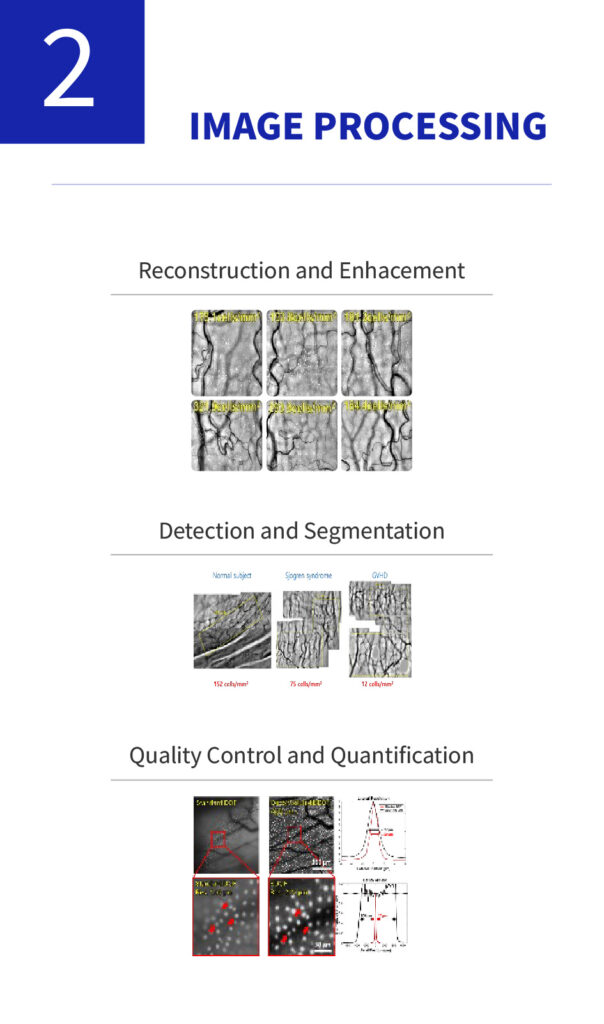

Dry eye disease occurs due to abnormalities in the tear film and is often accompanied by ocular discomfort and keratoconjunctivitis.The tear film consists of the mucin, aqueous, and lipid layers, and accurate diagnosis of the affected layer is essential for appropriate treatment of dry eye disease.Although methods exist to evaluate each layer of the tear film, there is still a lack of adequate techniques to specifically assess the mucin layer.

We have developed the world’s first imaging technology for conjunctival goblet cells, a core innovation that enables the diagnosis of various ocular diseases, including dry eye disease. Goblet cells serve as definitive biomarkers for dry eye and play a crucial role in maintaining immune tolerance. This breakthrough technology holds potential for expansion into diagnostics for other

Non-invasive, high-precision analytical technology